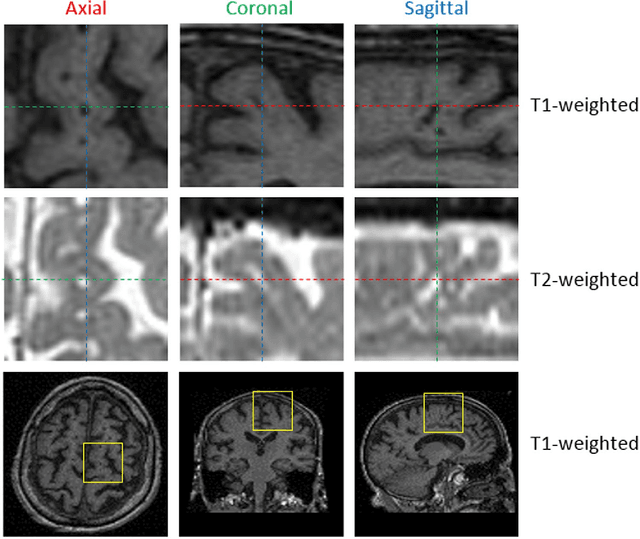

Abstract:Perivascular Spaces (PVS) are a recently recognised feature of Small Vessel Disease (SVD), also indicating neuroinflammation, and are an important part of the brain's circulation and glymphatic drainage system. Quantitative analysis of PVS on Magnetic Resonance Images (MRI) is important for understanding their relationship with neurological diseases. In this work, we propose a segmentation technique based on the 3D Frangi filtering for extraction of PVS from MRI. Based on prior knowledge from neuroradiological ratings of PVS, we used ordered logit models to optimise Frangi filter parameters in response to the variability in the scanner's parameters and study protocols. We optimized and validated our proposed models on two independent cohorts, a dementia sample (N=20) and patients who previously had mild to moderate stroke (N=48). Results demonstrate the robustness and generalisability of our segmentation method. Segmentation-based PVS burden estimates correlated with neuroradiological assessments (Spearman's $\rho$ = 0.74, p $<$ 0.001), suggesting the great potential of our proposed method